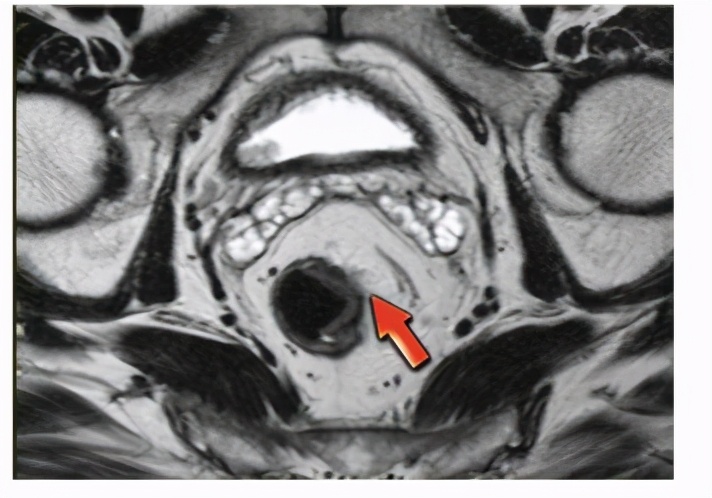

患者直肠癌术后1年半局部复发。术后病理看中期,T3N1b。术后做了辅助化疗。目前CT检查看应该是盆腔复发。对于局部复发的诊断,一般很难取到活检病理,因为复发病变位于直肠外,甚至盆腔侧方深在间隙,很难穿刺活检。主要依靠增强CT或者核磁共振,必要时可以结合PET/CT的表现。这个患者没有做术前放疗,客观上增加了局部复发风险。

直肠癌核磁共振表现可以显示肠壁增厚,肠周淋巴结肿大